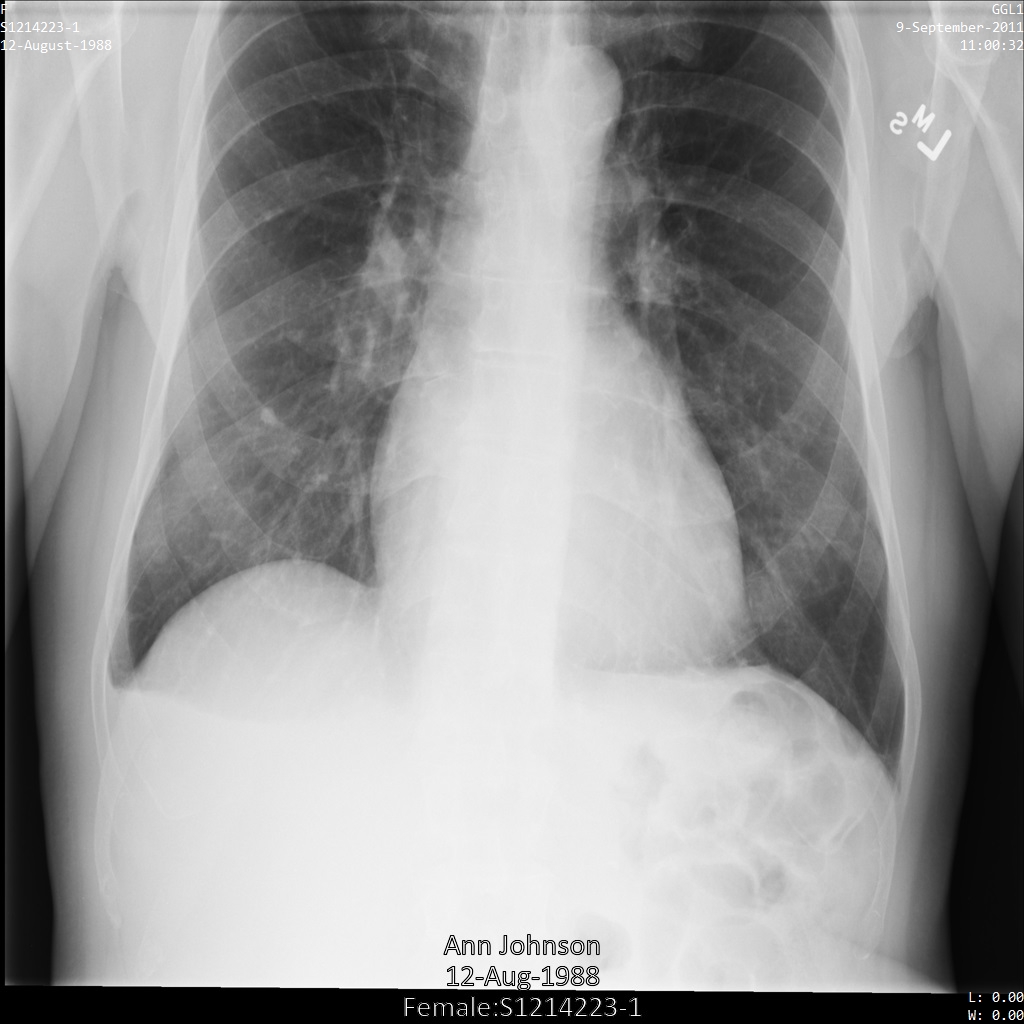

使用 ATTRIBUTE_CONFIDENTIALITY_BASIC_PROFILE 標記篩選設定檔將圖片提交給 Cloud Healthcare API 後,圖片看起來會如下所示。雖然圖片頂端角落顯示的中繼資料已遭塗銷,但圖片底部的 PHI 仍會保留。如要一併移除內建文字,請參閱「從圖片中遮蓋內建文字」。

使用 REDACT_ALL_TEXT 和 DEIDENTIFY_TAG_CONTENTS 選項將圖片提交給 Cloud Healthcare API 後,圖片看起來會如下所示。請注意下列異動:

- 圖片左上角和右上角的名稱已使用

CryptoHashConfig轉換 - 圖片左上角和右上角的日期已使用

DateShiftConfig轉換 - 圖片底部的內建文字已經過編輯

使用 DEIDENTIFY_TAG_CONTENTS 設定檔將圖片提交給 Cloud Healthcare API 後,圖片看起來會如下所示。

請注意下列異動:

- 圖片左上角和右上角的名稱已使用

CryptoHashConfig轉換 - 圖片左上角和右上角的日期已使用

DateShiftConfig轉換

使用 redactConfig 轉換將圖片提交給 Cloud Healthcare API 後,圖片看起來會如下所示:

使用 characterMaskConfig 轉換將圖片提交給 Cloud Healthcare API 後,圖片看起來會如下所示:

使用 dateShiftConfig 轉換將圖片提交給 Cloud Healthcare API 後,圖片看起來會如下所示:

使用 cryptoHashConfig 轉換將圖片提交給 Cloud Healthcare API 後,圖片看起來會如下所示:

使用 replaceWithInfoTypeConfig 轉換將圖片提交給 Cloud Healthcare API 後,圖片看起來會如下所示: